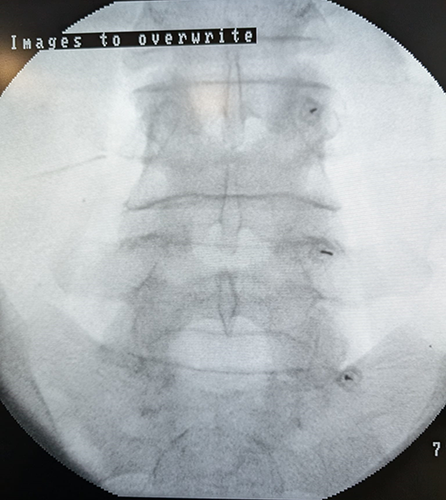

Rizólisis lumbar.

Imagen